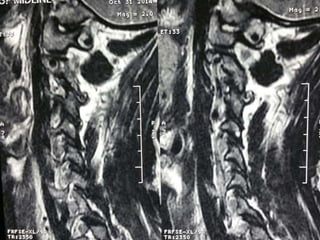

48 year old man with right fifth finger pain and numbess

S/P C7T1

ACDF

persistent

symptoms of

ataxia, neck

pain, fine

motor hand

dysfunction